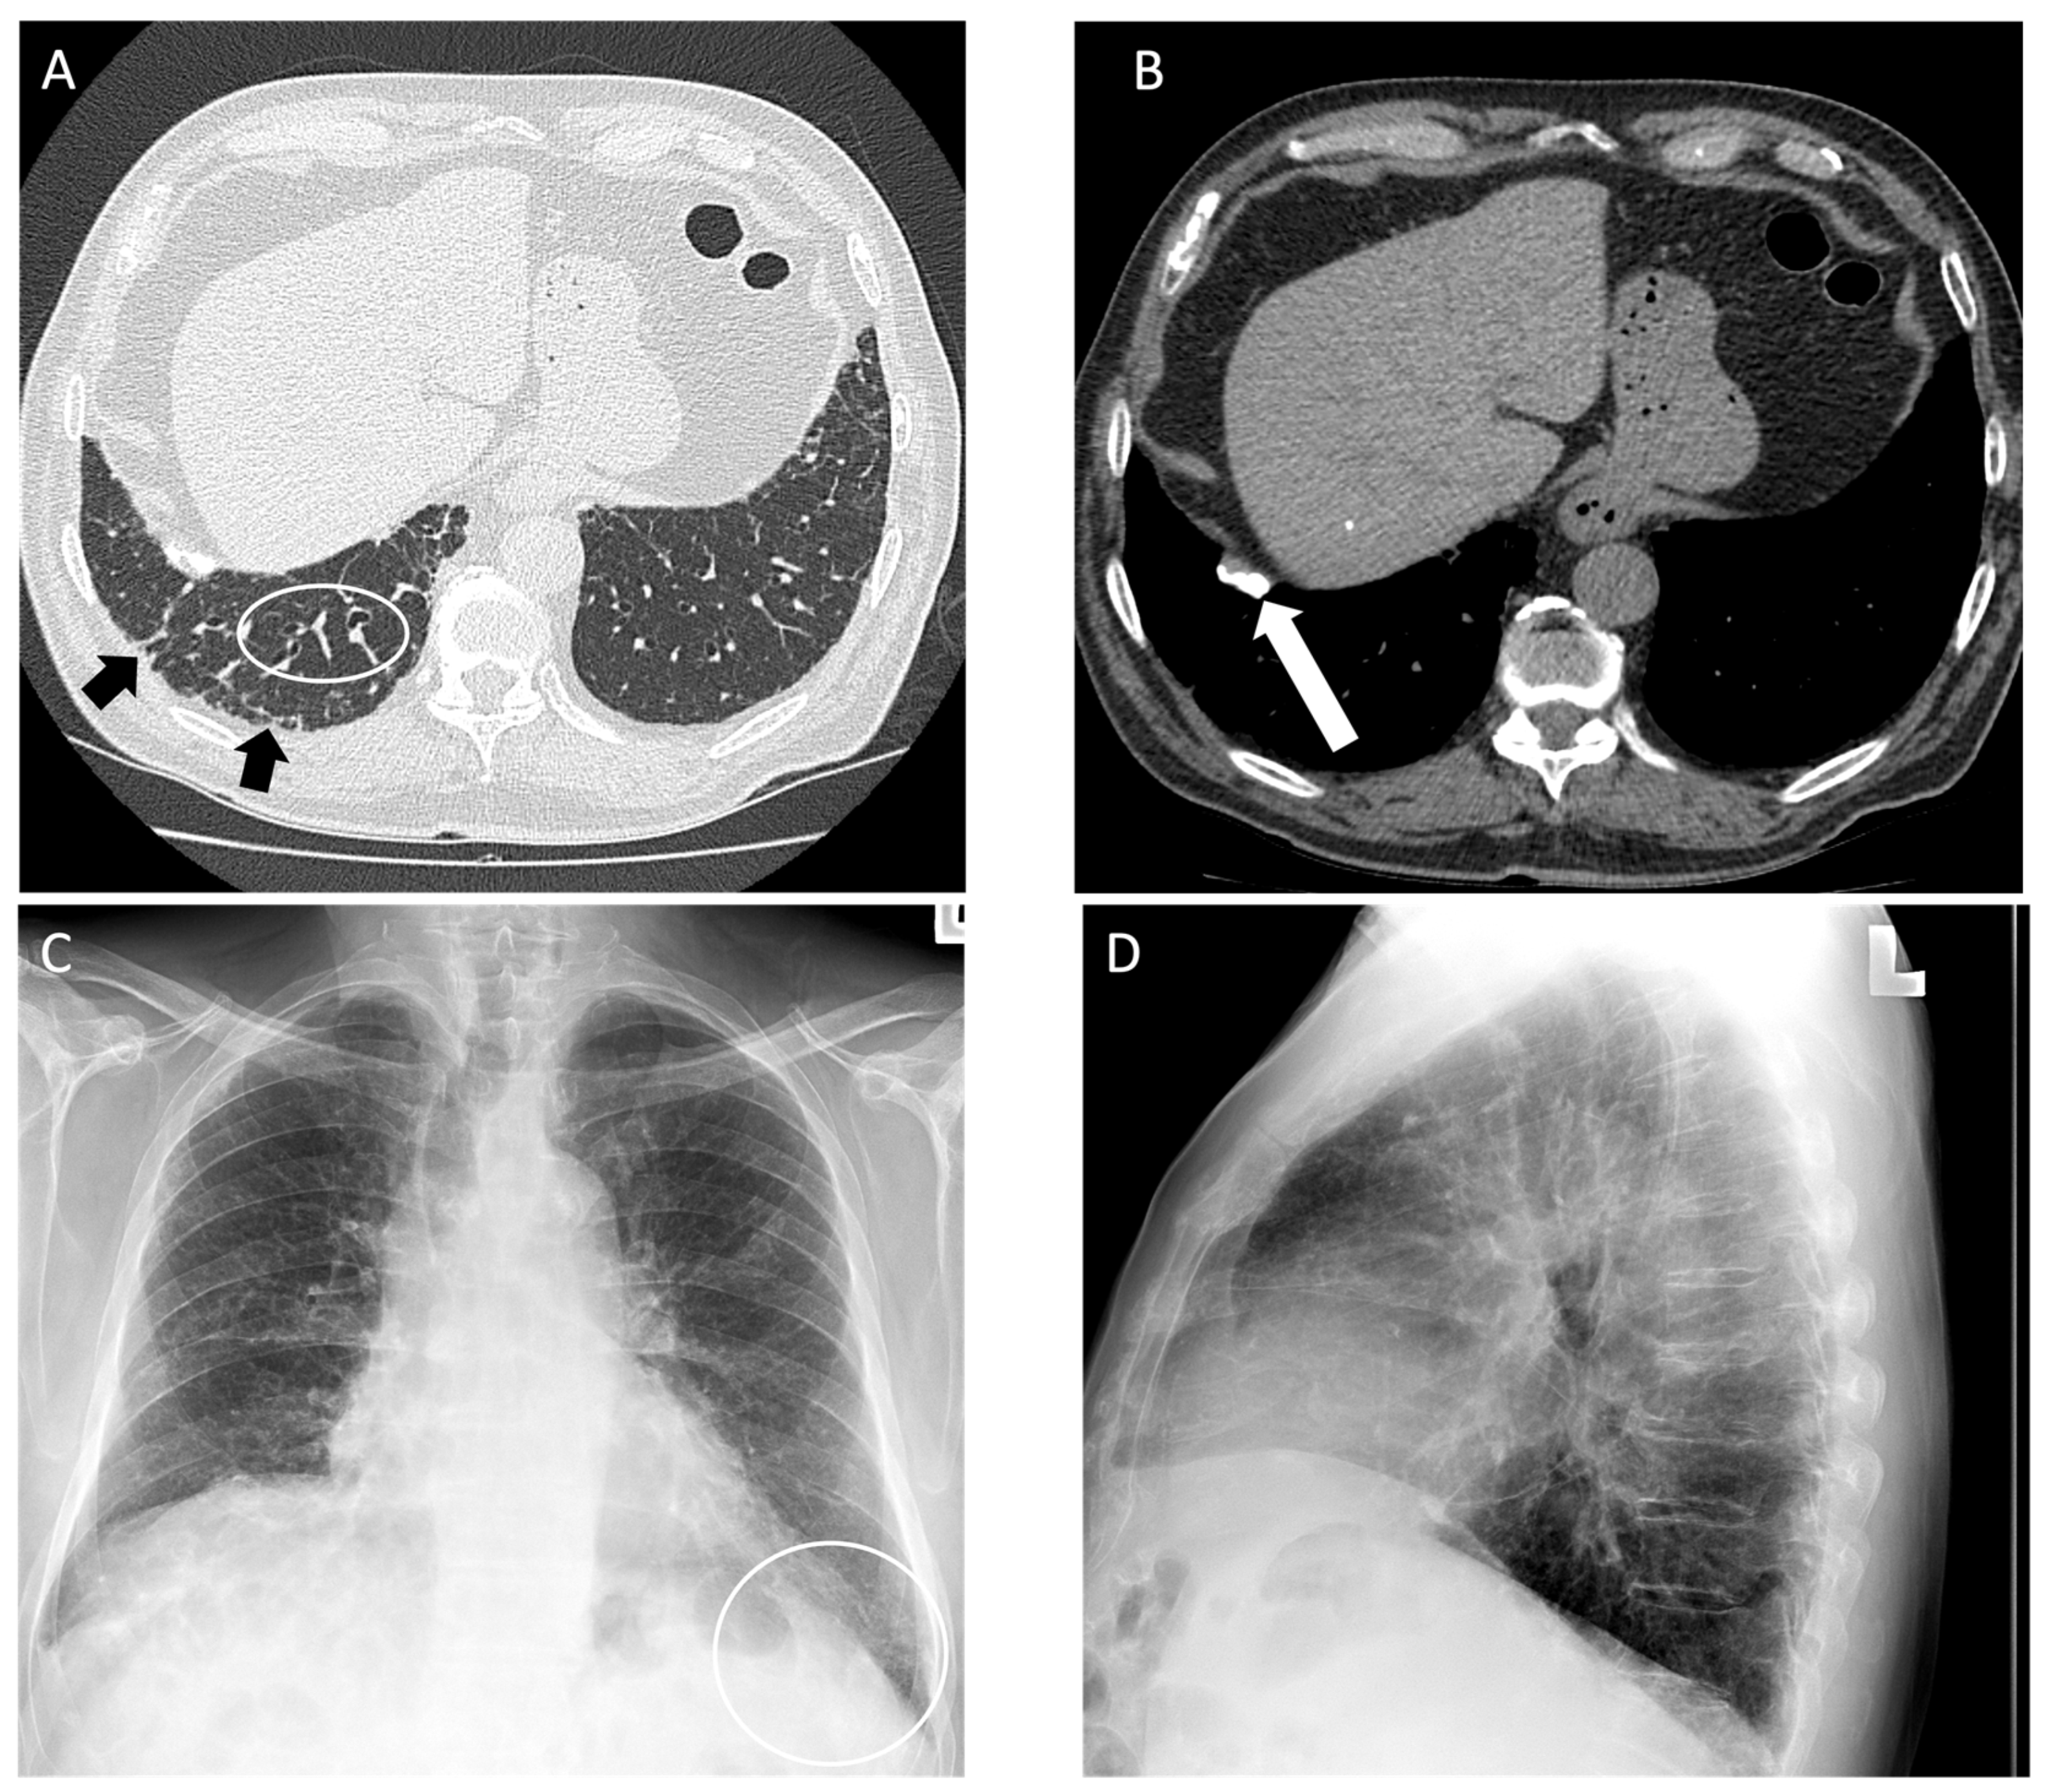

4.2. Coal Worker’s Pneumoconiosis

| Coal Worker’s Pneumoconiosis | Similar to simple or complicated silicosis, lymph node calcification is less common [34] | Difficult to differentiate by imaging only |